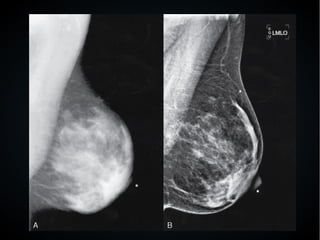

● En una radiografía vamos a ver 5 densidades

diferentes:

– Aire o gas densidad 1, la mas negra

– Grasa densidad 2, gris oscuro

– Líquidos y tejidos blandos densidad 3, gris mas

claro

– Huesos densidad 4, gris claro

– Metal densidad 5, blanco

● Cuanto mas negro, mas radiotransparente es la

estructura, y cuanto mas blanco, mas radiopaca.